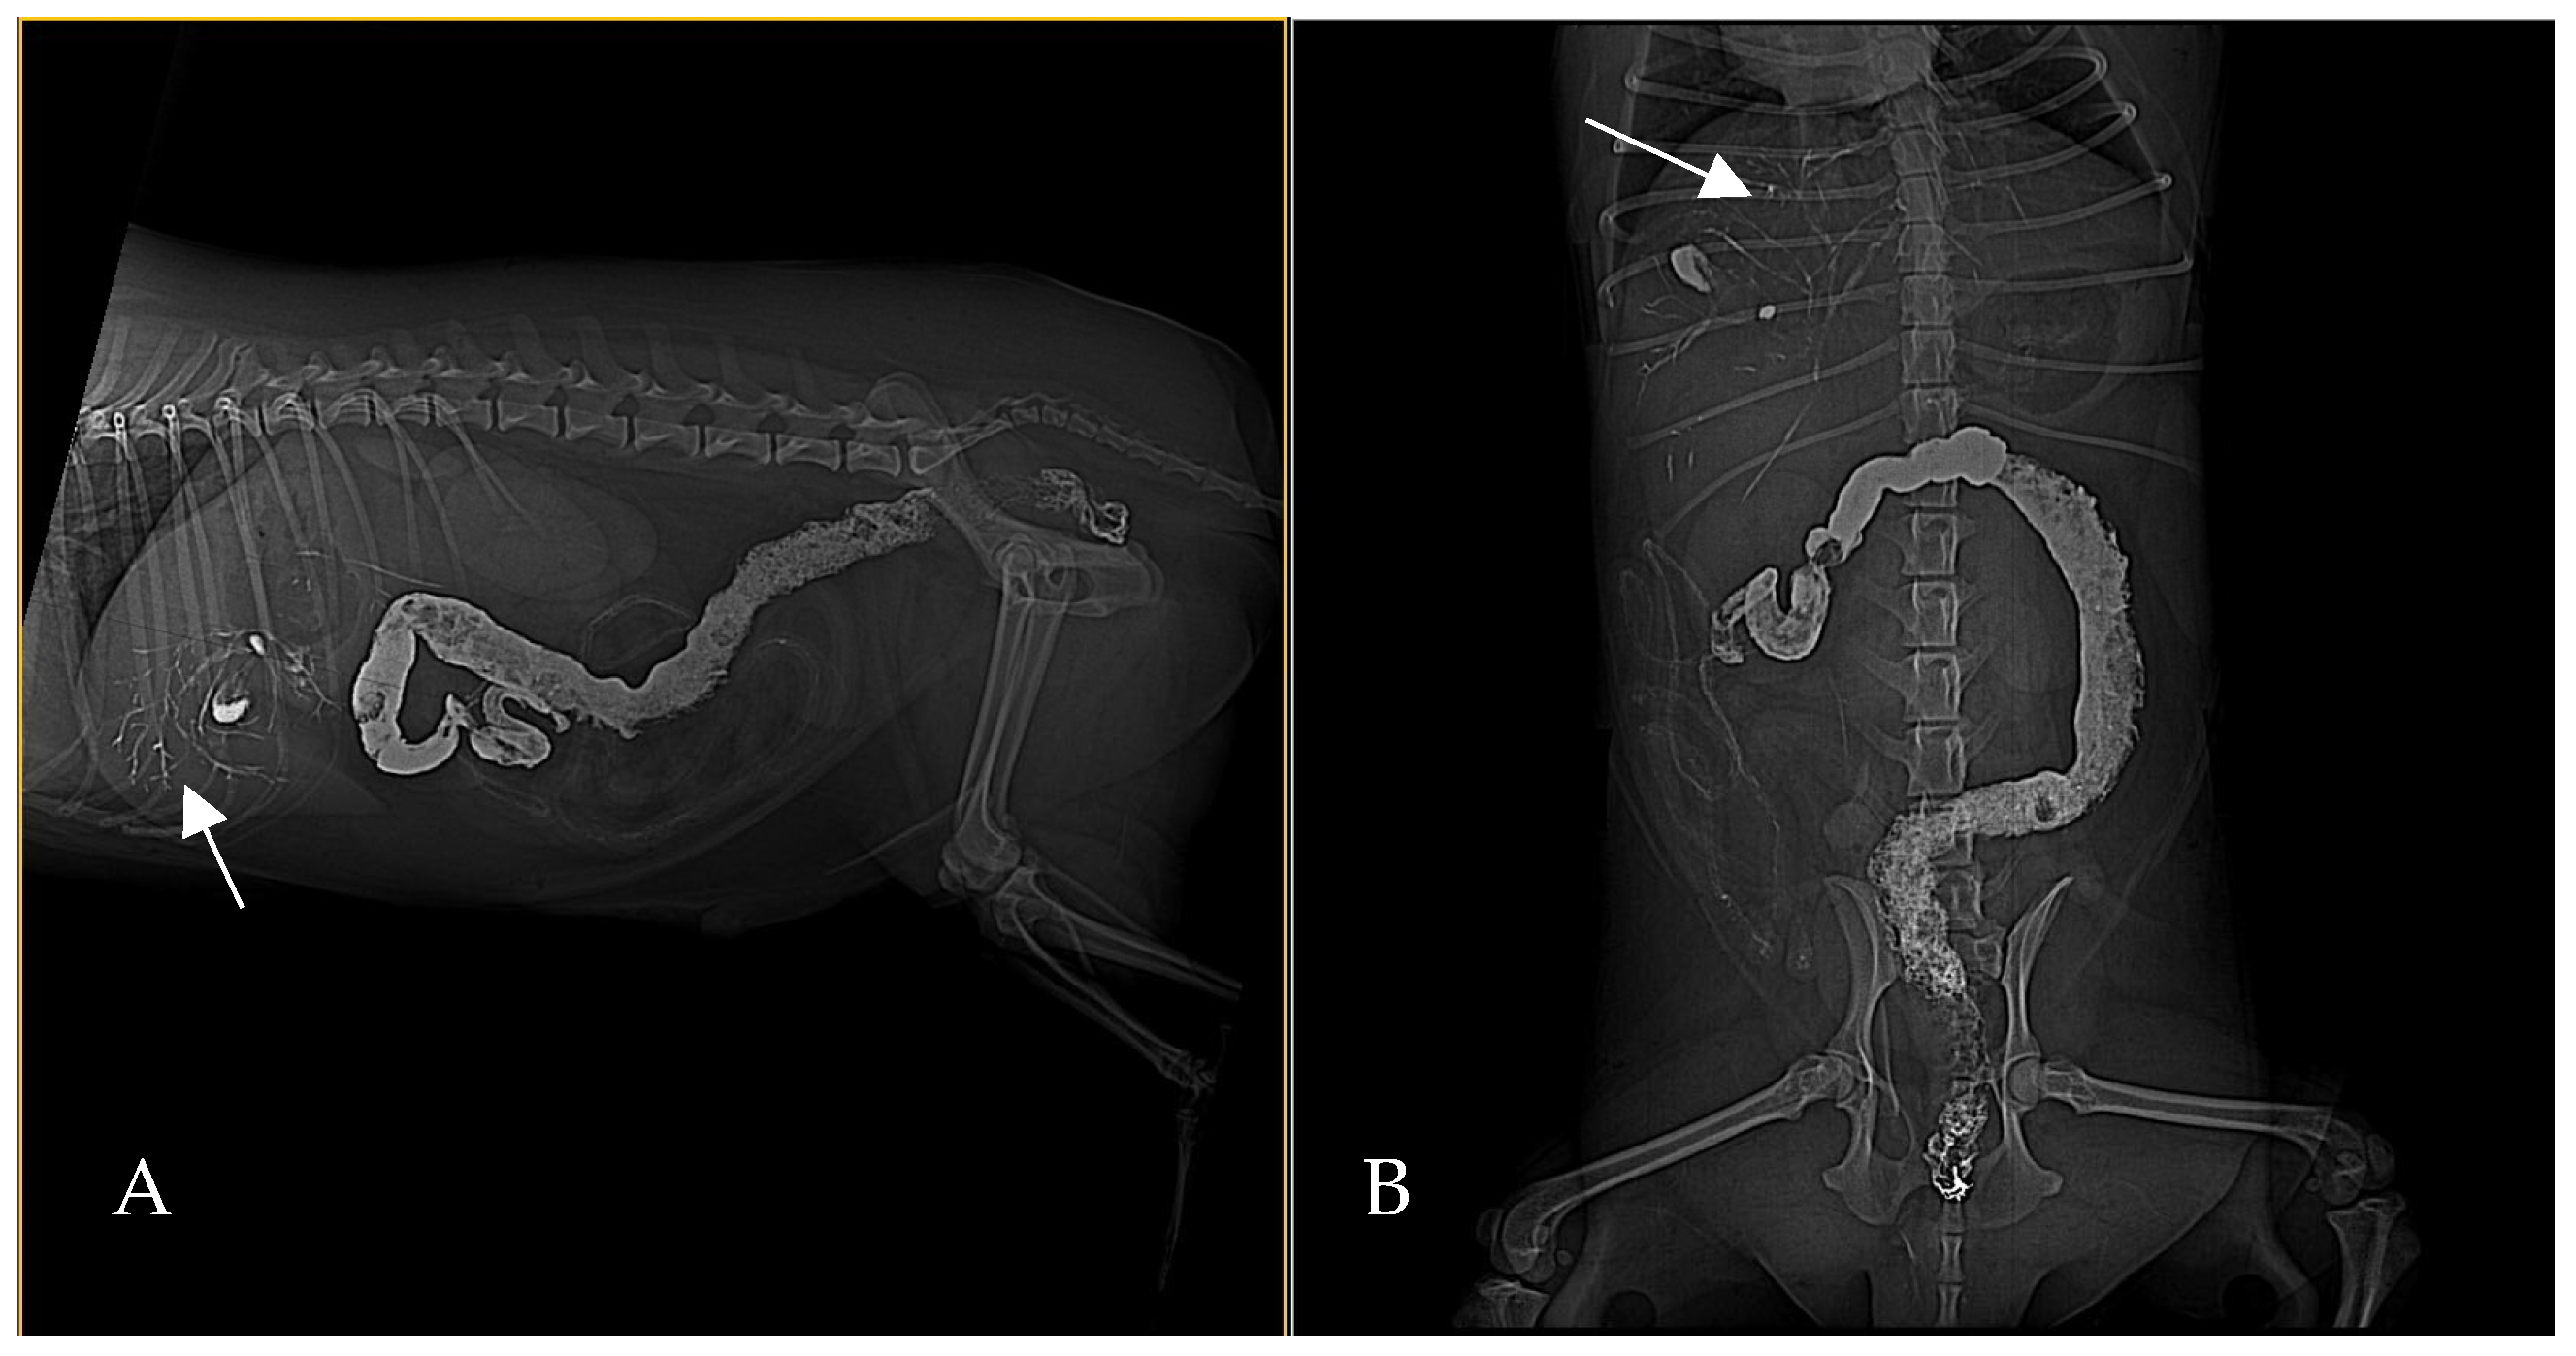

At 30 min post-barium, ventrodorsal and lateral radiographs demonstrated a barium-filled stomach with evident rugal folds and a small amount of barium that beginning to pass in the small intestines, with no biliary reflux of barium evident at that time (Figure 2). Gas was persistent in the biliary tree, appearing slightly more pronounced than on the initial radiograph.

Figure 2. Ventrodorsal (A) and lateral (B) abdominal radiograph, 30 min post-barium administration. The stomach is filled with barium (asterisk), and small amount of barium is visible in small intestines. There is no evidence of biliary reflux at this time. Gas persists in biliary tree ((B), white arrows).